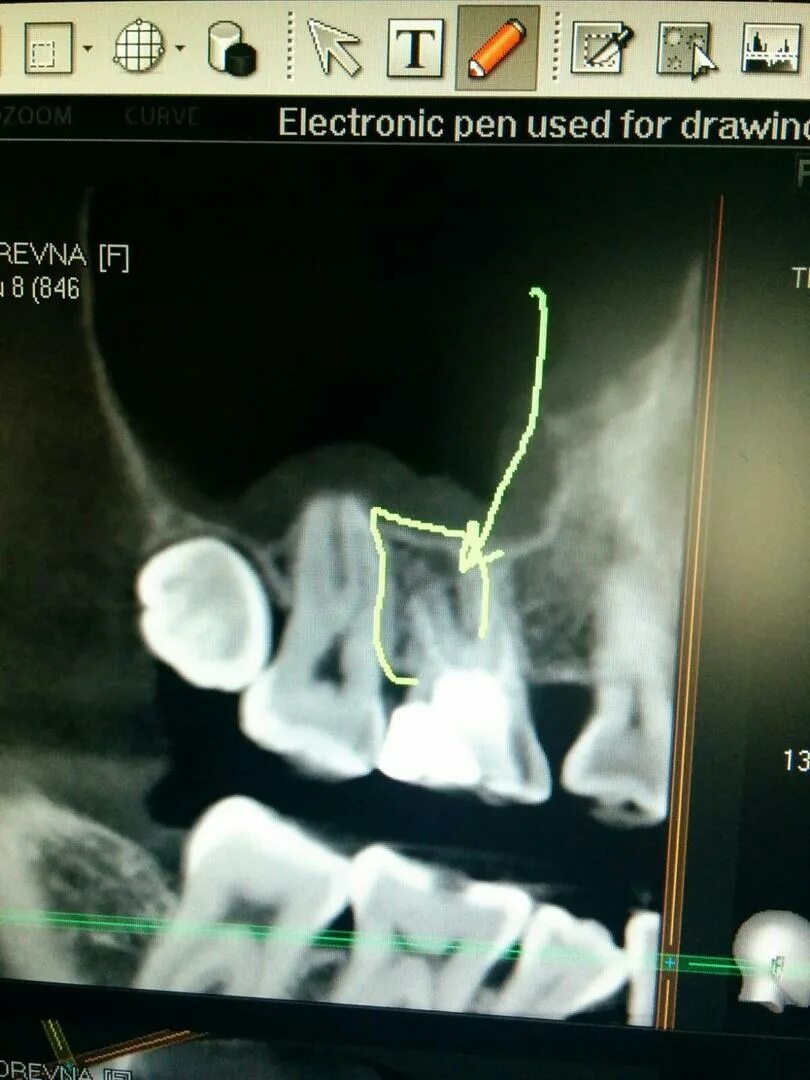

Зубной карман